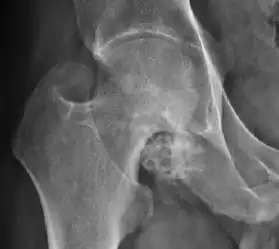

Plain radiography allows us to categorize the hip as normal or dysplastic or with impingement signs (pincer, cam, or a combination of both). Besides these, pathologic processes like osteoarthritis, inflammatory diseases, infection, or tumors can also be identified (Figure 1).[1]

Synovial chondromatosis can be confidently diagnosed by X-ray when calcified cartilaginous chondromas are seen. However, other synovial proliferative processes, such as pigmented villonodular synovitis, require MRI for accurate diagnosis, although noncalcified synovitis can be suspected in radiographs by indirect signs, such as soft tissue swelling and/or erosions in the femoral head, femoral neck, or acetabulum (Figure 7).[1]

X-ray of synovial chondromatosis.[1]

CT of synovial chondromatosis.[1]